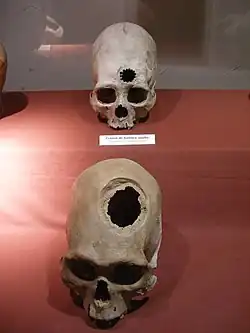

Trepanationen des Schädels wurden bei einer Vielzahl von historischen Kulturen und Gemeinschaften rund um den Globus praktiziert. Es gibt Belege, dass diese sogar in der Jungsteinzeit praktiziert wurde.[1] Diese Praxis hält bis zum heutigen Tage an, jedoch wird sie nur unter sehr limitierten Umständen und bei sehr wenigen Kulturen durchgeführt. Wenn der Patient das Verfahren überlebte, begann der Knochen langsam vom Rand des Trepanationsloches zum Zentrum zurückzuwachsen. Dieses neue Knochenwachstum war messbar dünner als der unbeschädigte Knochen, sodass Wissenschaftler trepanierte Schädel dahingehend untersuchen, ob der Schädel Anzeichen von Heilungsprozessen aufwies oder nicht. Unter den indigenen Völkern Südamerikas findet sich diese Behandlungspraxis am häufigsten bei den Andenzivilisationen, wie den Inka, wo sie häufig mit dem Auftreten von Schädeldeformation einhergeht. Jedoch wurden Trepanationen auch schon bei präinkaischen Kulturen durchgeführt. Laut John Verano stellt die Trepanation im alten Peru eines der größten Rätsel der Medizingeschichte dar. Von den indigenen Völkern selbst gibt es keine Aufzeichnungen dazu, obwohl man in keinem anderen Land der Welt so viele durchlöcherte Schädel gefunden hat und auch die Spanier die Schädelöffnungen in ihren frühen Kolonialberichten nicht erwähnten. Für Verano steht fest, dass die Inka ihren Eroberern in der Kunst der Schädelöffnung weit überlegen waren.[2]

Trepanationen traten in den südzentralen Anden im großen Stil erstmals ca. 200–600 n. Chr. auf[3] und wurden später von der Chimú-Kultur, die für ihre goldenen und metallenen Erzeugnisse berühmt ist, perfektioniert. Bei einer ersten Untersuchung von chirurgisch geöffneten Schädeln kam der Anthropologe Paul Broca (1824–1880) zu dem Schluss, dass im alten Peru „fortgeschrittene Chirurgie“ praktiziert wurde.[4] Die untersuchten Schädel wiesen Anzeichen von Heilungsprozessen an den Knochenrändern auf, womit belegt war, dass „erfolgreiche“[5] Schädelöffnungen durchgeführt wurden, bei denen die Patienten überlebten.[6] Diese Art von Schädelöffnungen wurde durchgeführt, um physiologische Störungen oder Schädelfrakturen zu beseitigen. Die Medizinmänner, die die Schädelöffnungen durchführten, bedienten sich dabei eines Tumi, eines metallenen Zeremonialmessers. Der Medizinmann präparierte den Schädel mit dem Tumi, ließ ihn bluten, um die Störung zu beseitigen und bedeckte die Stelle anschließend mit einer Goldplatte.[7] Nicht nur das Tumi kam bei den Operationen zum Einsatz, sondern auch Bronzewerkzeuge sowie feine Kupfernadeln. Jeder sechste Schädel, den die Forscher untersuchten, wies mindestens ein Trepanationsloch auf.[2] Im extremsten Fall wurden bis zu sieben Löcher in einem Schädel gefunden, wobei viele Löcher eine nahezu perfekte Kreisform aufweisen.[8] Laut John Verano gebe es eine Grabstätte, bei der 50 % aller Männer, 30 % aller Frauen und 30 % aller Jugendlichen Trepanationslöcher in den Schädeln hätten. Sehr häufig weisen gefundene Schädel zusätzlich zu Schädelöffnungen einen hohen Grad an Deformität auf. Der älteste gefundene Schädel mit einem Trepanationsloch stammt aus der Zeit um 400 v. Chr.[2] Im alten Peru wurde die chirurgische Schädelöffnung sehr viel häufiger als im alten Europa praktiziert und wurde von „peruanischen Medizinmännern“ perfektioniert, was sich anhand einer signifikant hohen Überlebensquote der Operierten belegen lässt.[2] Zur Zeit der Expansion des Inka-Imperiums überlebten mehr als 90 % der Patienten.[8][2][9][10] Archäologen fanden Schädel, bei denen bis zu fünf Trepanationen vollständig verheilt waren. Eine im Jahr 2018 veröffentlichte Studie berichtet von – in archäologischen Stätten der Inka gefunden – Schädeln, bei denen bis zu sieben Trepanationen erfolgreich durchgeführt wurden.[11] Durch den Einsatz verschiedener Substanzen zur Desinfektion wie Saponin, Zimtsäure und Corilagin entzündete sich die Wunde nur in 4,5 Prozent der Fälle (siehe auch Medizin der Inka).[2] Heutzutage lassen sich viele trepanierte Schädel im Museo Regional De Ica in Ica betrachten.[12]

Deformierter und trepanierter Schädel

Deformierter und trepanierter Schädel -